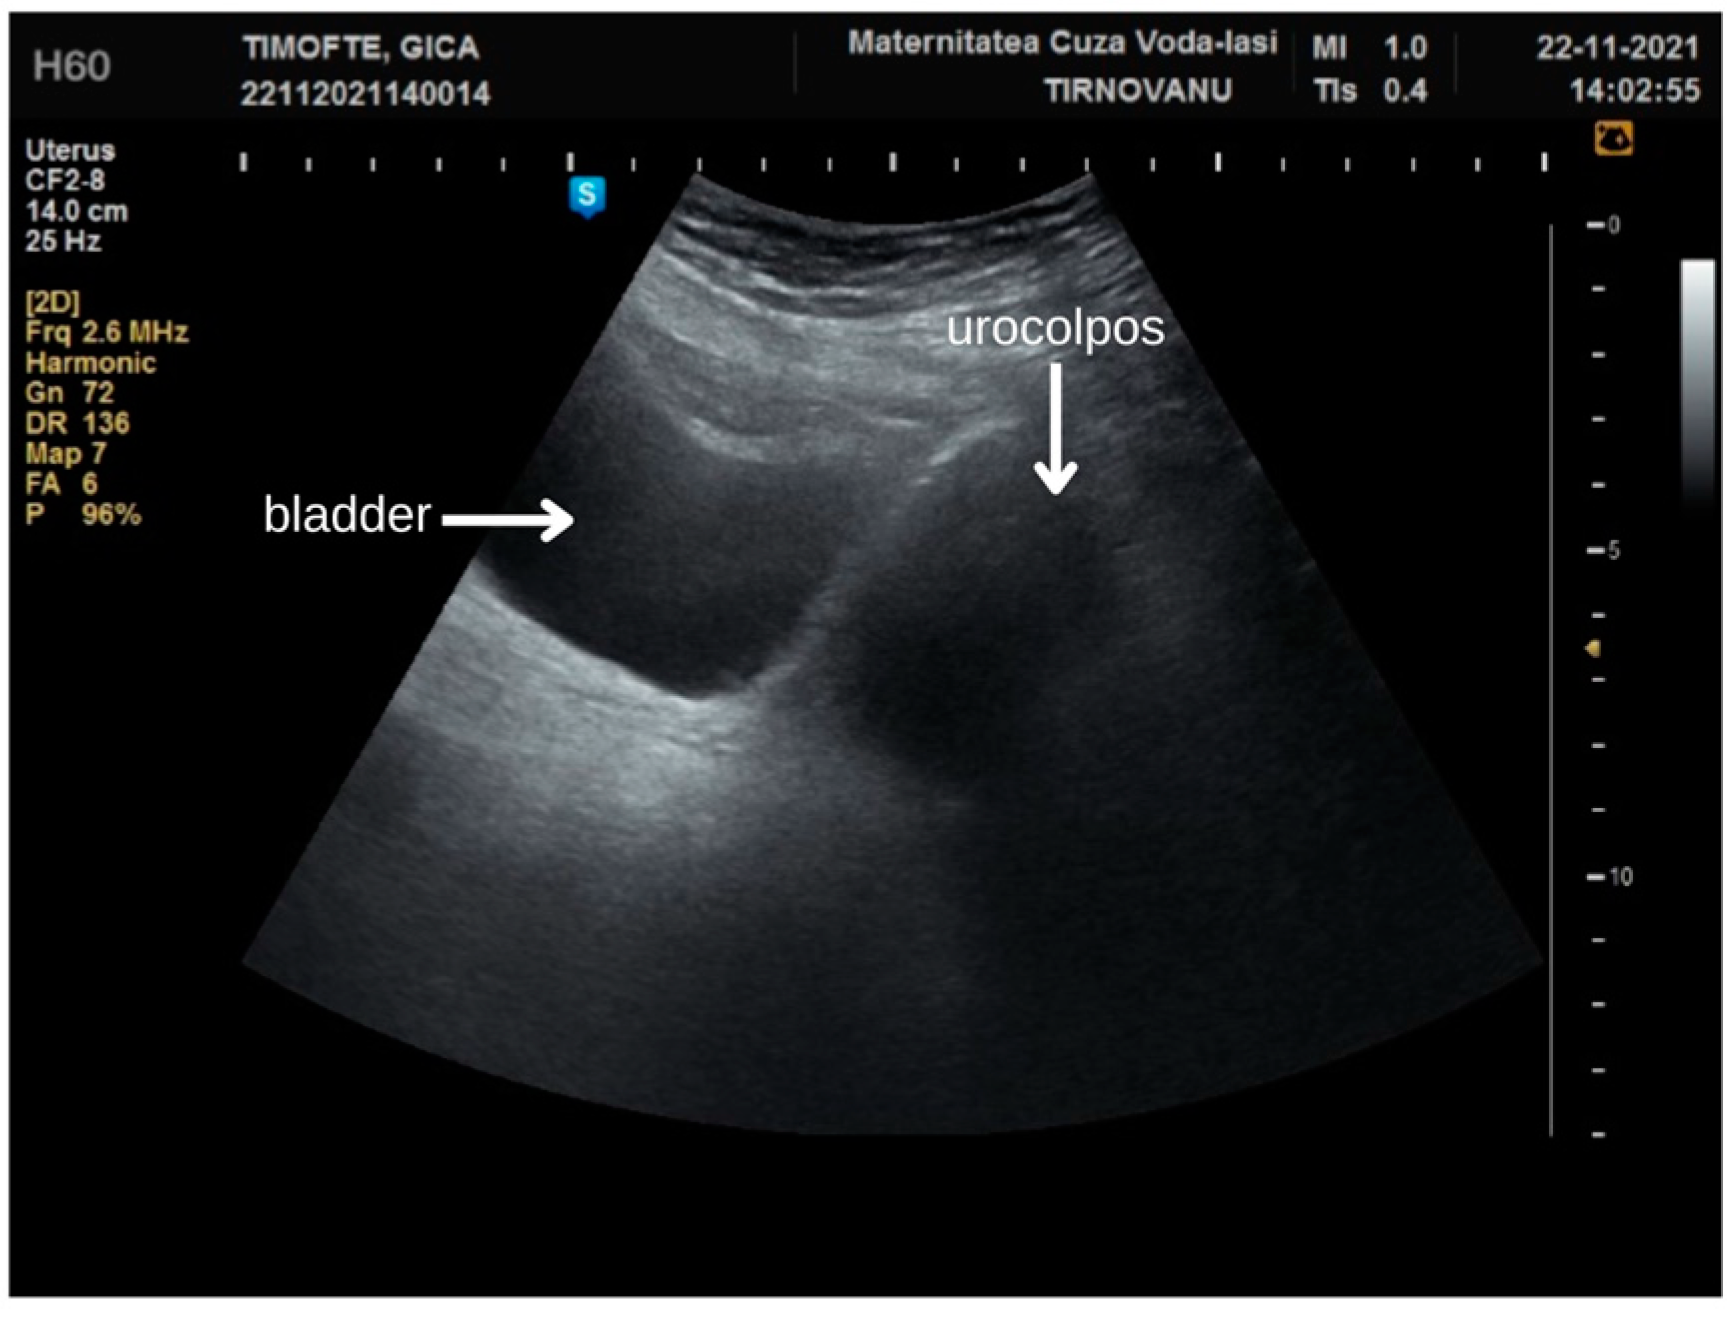

Her surgical history was significant, including a procedure in 2021 for complete fusion of the labia majora, approximately two and a half years prior to the current admission. During that hospitalization, she experienced complete urinary retention for about three days. This symptom was attributed to the accumulation of urine in a blind pocket formed by the adhesions, which would subsequently leak onto her undergarments post-voiding. During the surgical procedure, a urinary tract infection with Escherichia coli was identified via bladder catheterization. The anatomical region affected by the synechia had formed a pocket, predisposing it to urine retention and microbial proliferation. In the middle third of the labial coalescence, a 5 mm membrane allowed for urine to exit during abdominal compression. An abdominal ultrasound examination revealed urine in both the bladder and the urocolpos (Figure 2), along with bilateral hydronephrosis classified as grade I. We successfully inserted a urinary catheter into the vagina, which resulted in the discharge of 1.5 L of urine.

Figure 2. Ultrasound at first admission for labial fusion.